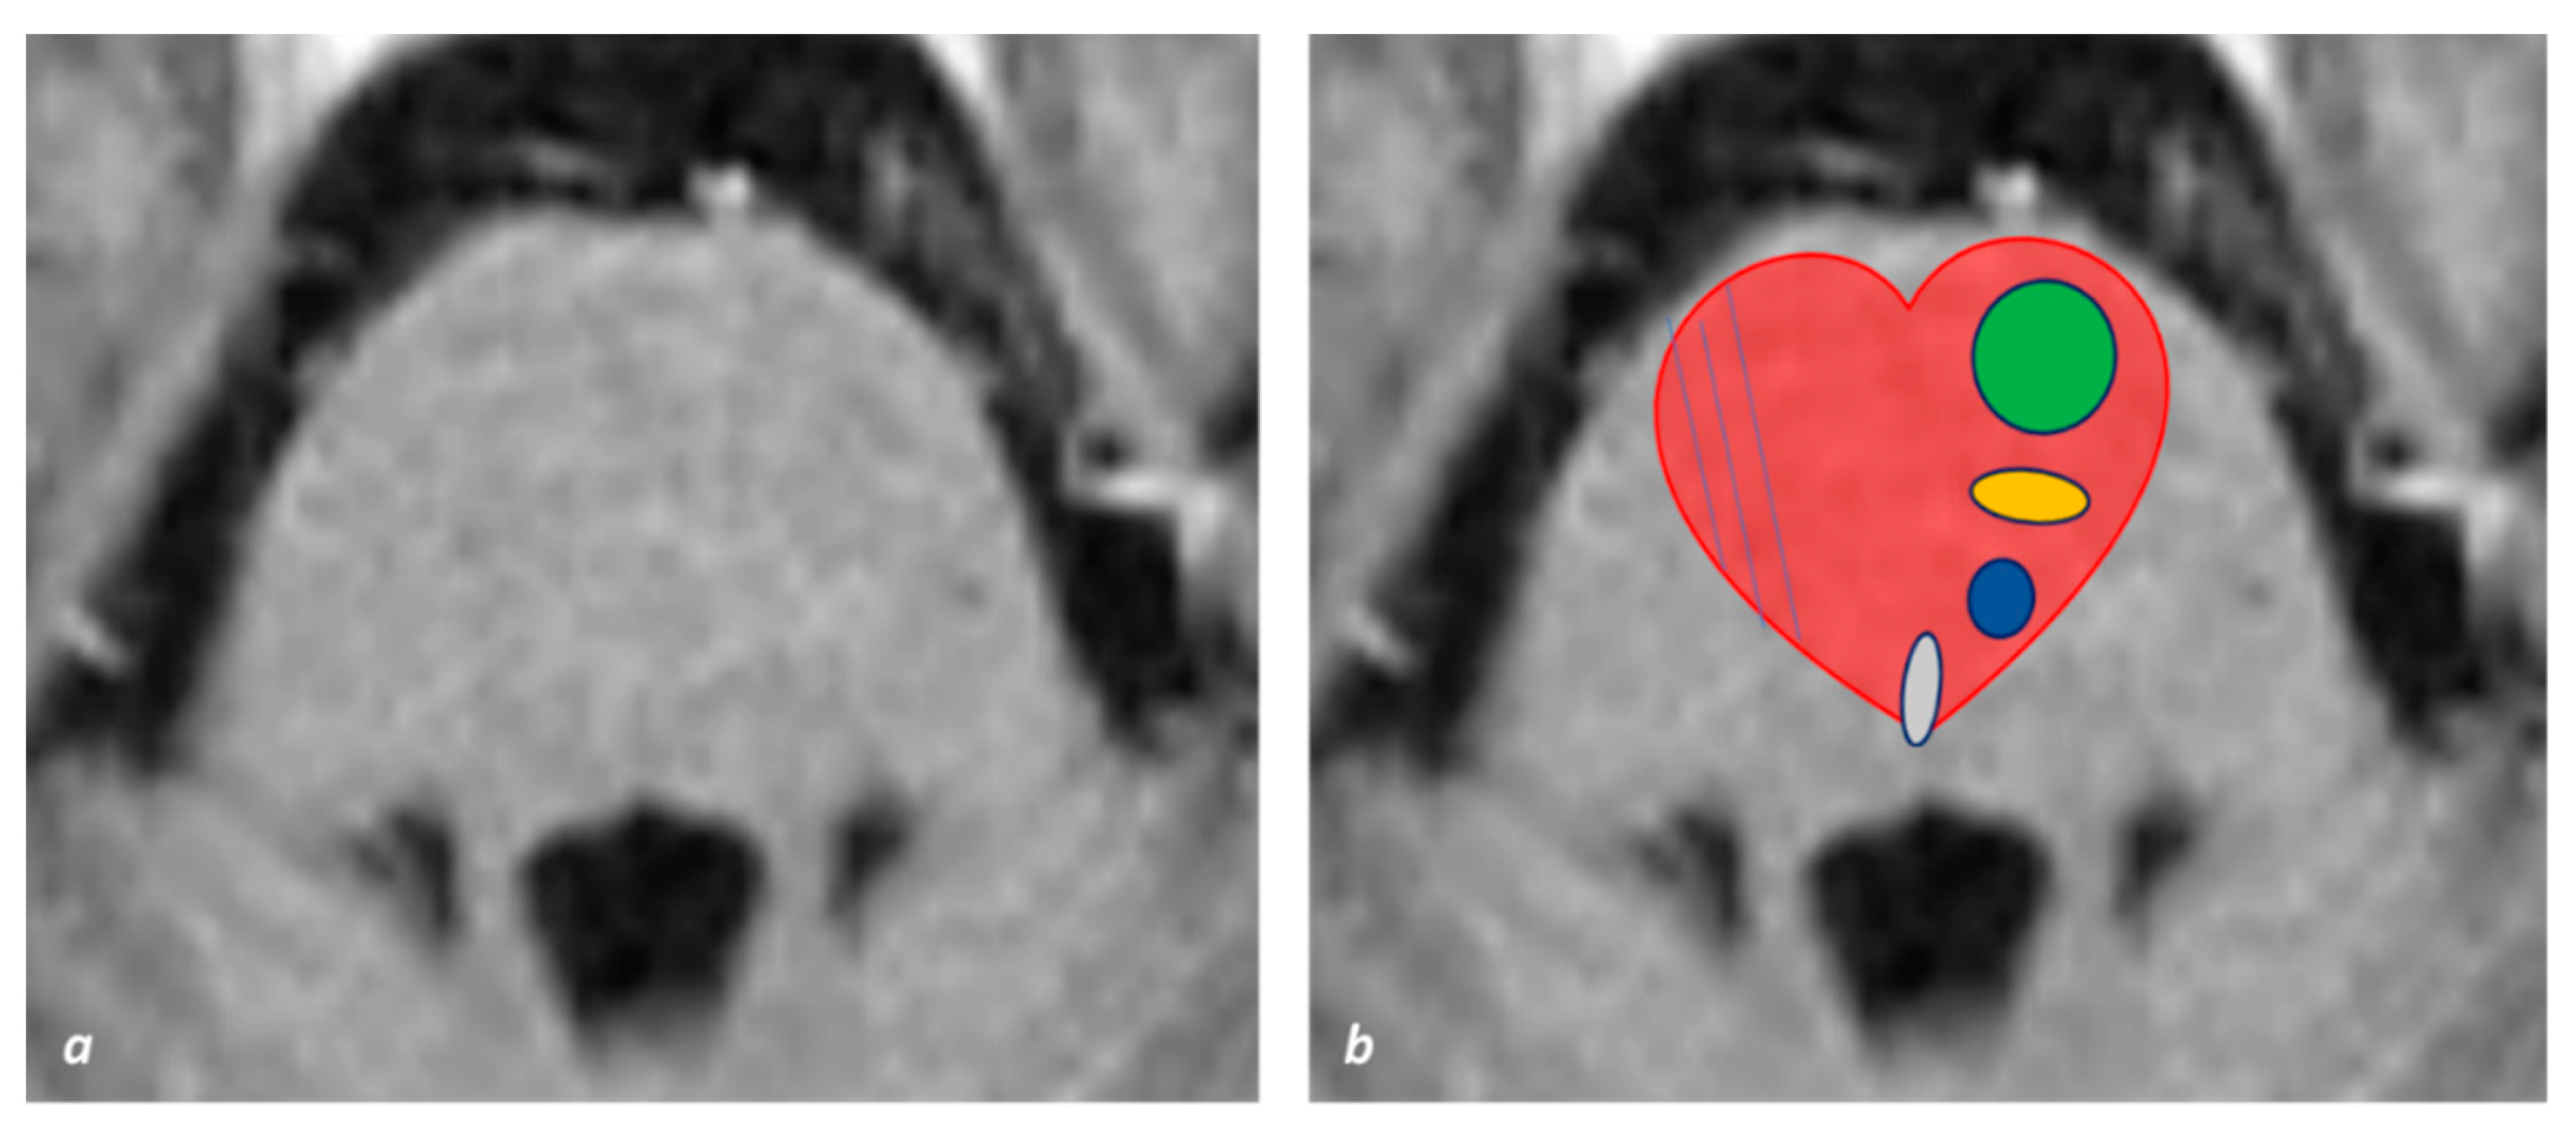

- Tokuoka, K.; Yuasa, N.; Ishikawa, T.; Takahashi, M.; Mandokoro, H.; Kitagawa, Y.; Takagi, S. A case of bilateral medial medullary infarction presenting with “heart appearance” sign. Tokai J. Exp. Clin. Med. 2007, 32, 99–102. [Google Scholar]

- Maeda, M.; Shimono, T.; Tsukahara, H.; Maier, S.E.; Takeda, K. Acute Bilateral Medial Medullary Infarction: A Unique ‘Heart Appearance’ Sign by Diffusion-Weighted Imaging. Eur. Neurol. 2004, 51, 236–237. [Google Scholar] [CrossRef]

- Thijs, R.D.; Wijman, C.A.C.; van Dijk, G.W.; van Gijn, J. A case of bilateral medial medullary infarction demonstrated by magnetic res-onance imaging with diffusion-weighted imaging. J. Neurol. 2001, 248, 339–340. [Google Scholar] [CrossRef]

- Venkatesan, P.; Balakrishnan, R.; Ramadoss, K.; Iyer, R.S. Heart appearance sign in pontine stroke: A result of bilateral infarction due to small vessel disease. Neurol. India 2014, 62, 115–116. [Google Scholar] [CrossRef]

- Sen, D.; Arora, V.; Adlakha, S.; Gulati, Y.S.; Doppaladudi, A.; Tiwary, S. The “Heart Appearance” Sign in Bilateral Pontine Infarction. J. Stroke Cerebrovasc. Dis. 2015, 24, e21–e24. [Google Scholar] [CrossRef]

- Zhou, C.; He, Y.; Chao, Z.; Zhu, Y.; Wang, P.; Gao, X. The “heart appearance” sign on MRI of Wernekink’s commissure syndrome caused by bilateral caudal paramedian midbrain infarction. Neurol. Sci. 2017, 39, 587–589. [Google Scholar] [CrossRef] [PubMed]

- Krishnan, M.; Rajan, P.; Kesavadas, C.; Iyer, R.S. The ‘heart appearance’ sign in MRI in bilateral medial medullary infarction. Postgrad. Med. J. 2011, 87, 156. [Google Scholar] [CrossRef]